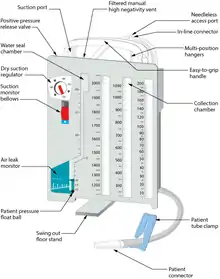

Chest drainage system

A chest drainage system is typically used to collect chest drainage (air, blood, effusions). Most commonly, drainage systems use three chambers which are based on the three-bottle system. The first chamber allows fluid that is drained from the chest to be collected. The second chamber functions as a "water seal", which acts as a one way valve allowing gas to escape, but not reenter the chest. Air bubbling through the water seal chamber is usual when the patient coughs or exhales but may indicate, if continual, a pleural or system leak that should be evaluated critically. It can also indicate a leak of air from the lung. The third chamber is the suction control chamber. The height of the water in this chamber regulates the negative pressure applied to the system. A gentle bubbling through the water column minimizes evaporation of the fluid and indicates that the suction is being regulated to the height of the water column. In this way, increased wall suction does not increase the negative pressure of the system. Newer drainage systems eliminate the water seal using a mechanical check-valve, and some also use a mechanical regulator to regulate the suction pressure. Systems which employ both these are dubbed "dry" systems, whereas systems that retain the water seal but use a mechanical regulator are called "wet-dry" systems. Systems which use a water seal and water column regulator are called "wet" systems. Dry systems are advantageous as tip-overs of wet systems can spill and mix with blood, mandating the replacement of the system. Even newer systems are smaller and more ambulatory so the patient can be sent home for drainage if indicated.[5]

More recently digital or electronic chest drainage systems have been introduced. An onboard motor is used as vacuum source along with an integrated suction control canister and water seal. These systems monitor the patient and will alert if the measured data are out of range. Due to the digital control of the negative pressure, the system is able to objectively quantify the presence of a pleural or system leak. Digital drainage systems allow clinicians to mobilize patients early, even for those on continuous suction, which is difficult to accomplish with the traditional water-seal system under suction.[10][18] Recently published clinical data indicates, that application of such systems can also lead to a reduction in complications.[19][20]